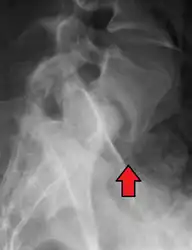

MRI of L5-S1 anterolisthesis

Anterolisthesis L5/S1